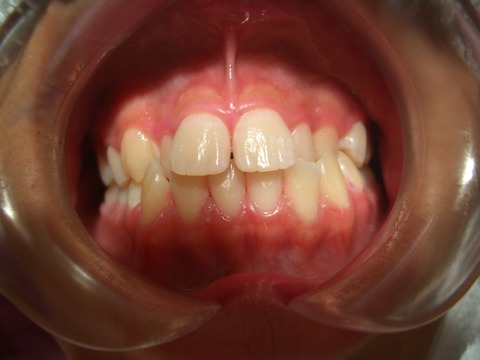

治療開始 2010.8.2 (中学2年生)